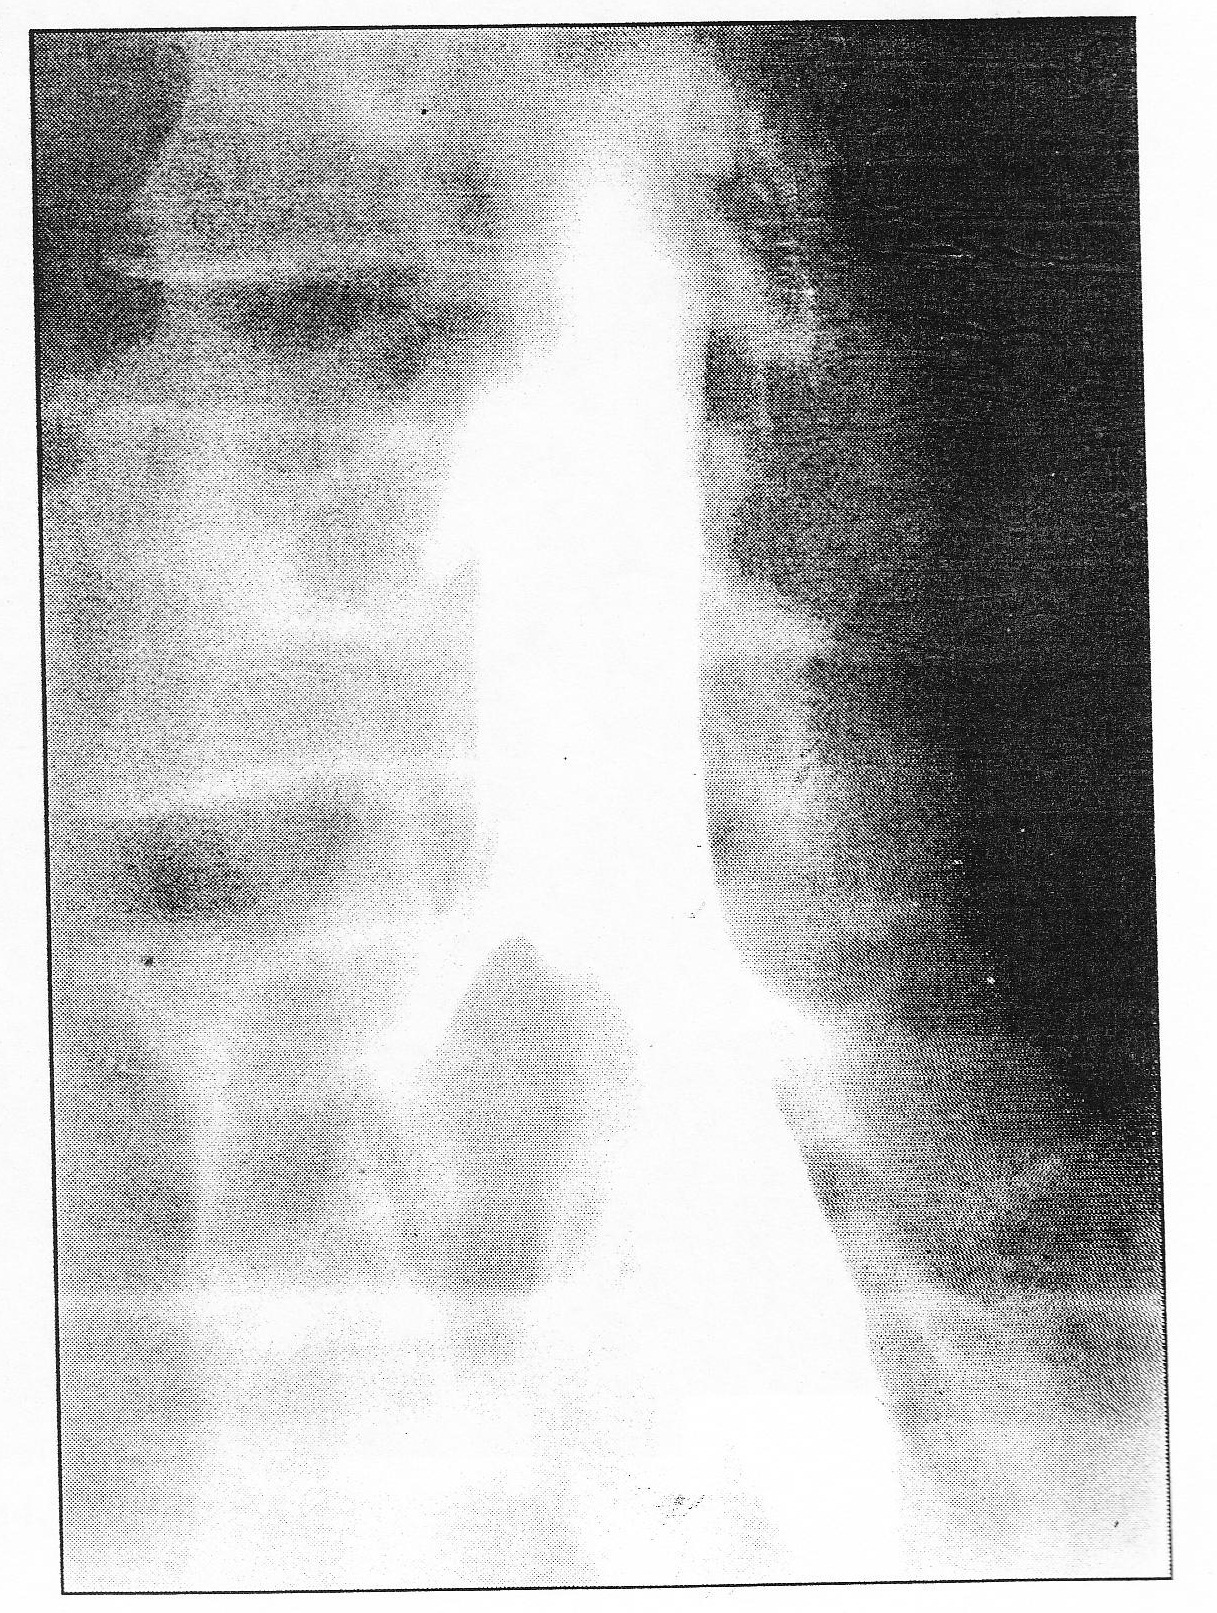

A. L4-5 central disc herniation wth compressin of both L5 nerve roots’

B. left L4-5 paracentral disc herniation with compression of L5 nerve root

C. left L5-S1 far lateral disc herniation with L5 nerve root compression

D. left L5-S1 paracentral disc herniation with S1 nerve root compression

E. left L4- S1 far lateral disc herniation with L4 nerve root compression